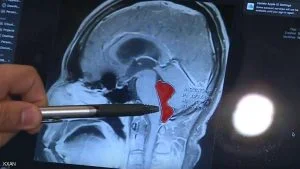

ووفقا لشبكة “إن بي سي” الإخبارية الأميركية، فإن المختصين اكتشفوا وجود دودة شريطة تنمو في دماغ الرجل منذ 10 سنوات، بعد إجراء الأشعة اللازمة، ونجحوا في إخراجها بجراحة دقيقة.

وتوصل الأطباء إلى أن الدودة دخلت جسم جيراردو عندما تناول وجبة من لحم الخنزير غير المطهو جيدا في المكسيك، قبل أكثر من 10 سنوات.